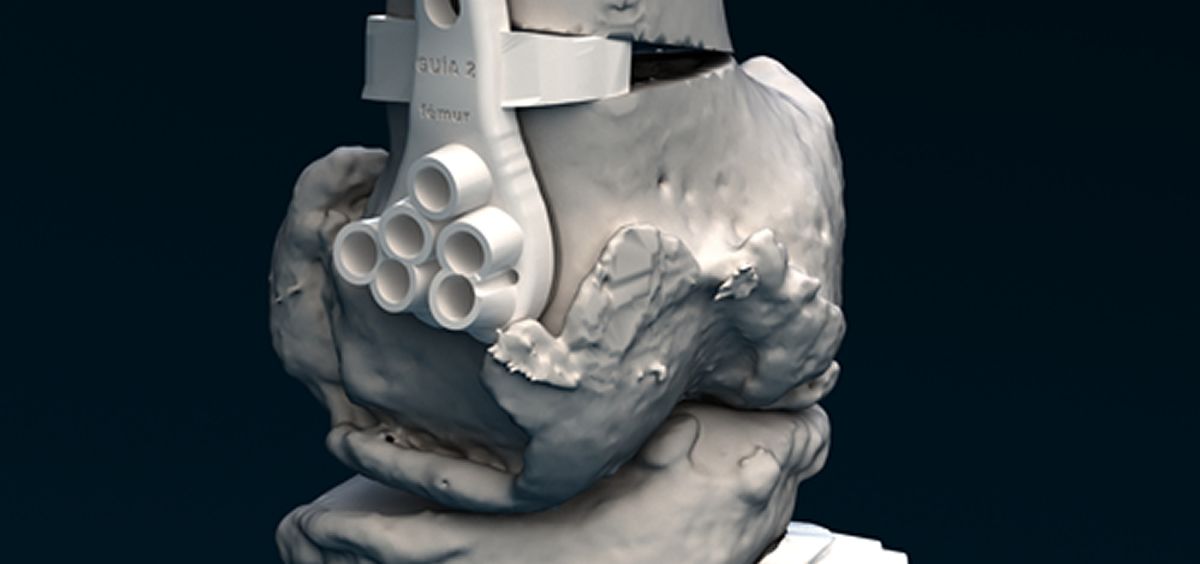

Las impresoras certificadas para producto sanitario exigidas en el nuevo MDR, como las utilizadas por Customimplants, garantizan la estanqueidad y el control de partículas, generándose una cámara de nitrógeno para que el proceso esté libre de oxígeno y eliminando un posible riesgo de contaminación de las piezas. Los biomodelos y guías de la empresa son fabricadas mediante sinterizado selectivo por láser, utilizando poliamida biocompatible, un material de dureza extrema, alta biocompatibilidad, ligero y poco higroscópico. El polvo blanco es sometido a un preprocesado previo a su introducción en la impresora, y éste será el color de las guías que utilice el cirujano en quirófano, ya que la normativa impide tintarlas si van a entrar en contacto con sangre.